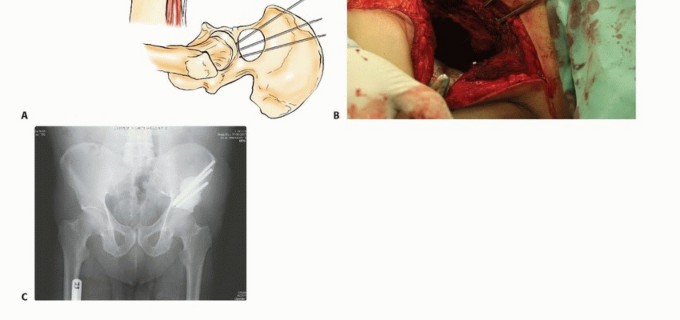

في بعض الأحيان، قد لا تؤثر هذه النقائل على استقرار ووظيفة الحوض بشكل مباشر، خاصة إذا كانت في مناطق مثل عظم الحرقفة أو العانة. ومع ذلك، فإن الأورام التي تصيب الجزء الخلفي من عظم الحرقفة قد تهدد سلامة المنطقة العجزية القطنية، بينما تلك التي تصيب التجويف الحقي (الحُق) يمكن أن تضعف بشكل كبير وظيفة مفصل الورك وقدرة الطرف السفلي على تحمل الوزن، مما يستدعي تدخلًا جراحيًا دقيقًا ومخططًا بعناية.

يُعد الأستاذ الدكتور محمد هطيف، بخبرته الواسعة التي تتجاوز 20 عامًا ودقته المتناهية في جراحة العظام، الرائد الأول في علاج نقائل الحوض في صنعاء واليمن. بصفته أستاذًا في جامعة صنعاء، يتبنى الدكتور هطيف منهجًا شاملاً يركز على استعادة وظيفة المريض وتخفيف الألم وتحسين نوعية حياته، باستخدام أحدث التقنيات الجراحية وأفضل الممارسات العالمية. يُدرك الدكتور هطيف أن الأورام اللحمية الأولية والأورام النقائلية غالبًا ما تتمدد بشكل كبير إلى الأنسجة الرخوة المحيطة، ولكن نظرًا لحساسيتها المتأصلة للعلاج الإشعاعي، فإن الإدارة الجراحية للآفات النقائلية لا تتطلب بالضرورة استئصالًا كاملاً للعضلات المغطية، حيث يمكن معالجة البقايا المجهرية بالإشعاع المساعد بعد الجراحة. يتطلب التشريح المعقد للحوض تخطيطًا تفصيليًا قبل الجراحة، وتحديدًا لتقنية التعرض وإعادة البناء، وتنفيذًا دقيقًا ومتقنًا للإجراء الجراحي لضمان أفضل النتائج للمريض.